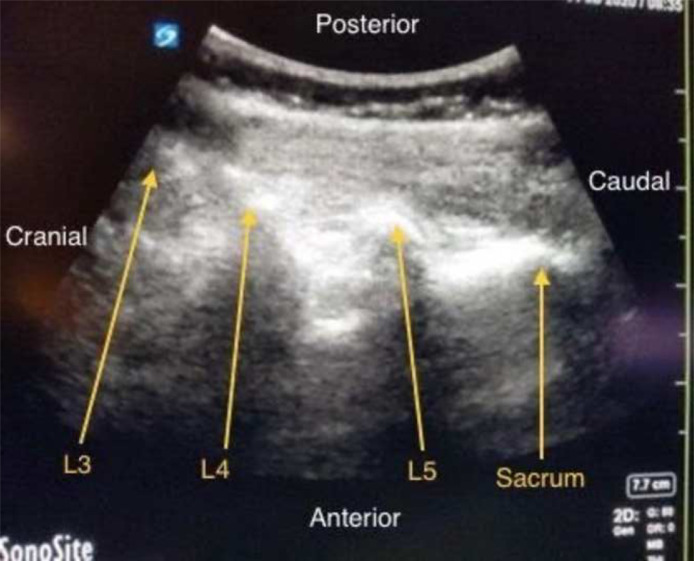

Upon examination of her outside medical records, the patient's most recent Computer Tomography (CT) scan had showed comminuted fracture of the L3 vertebra and noted a focal mild kyphotic curvature centered at L3. Mild retropulsion of osseous fragments as well as scattered discrete punctate densities, presumably osseous fragments, within the spinal canal were also noted with narrowing of the spinal canal at L3. On physical examination, the patient did have complete numbness at the L3 and L4 level on the right side, had 2/5 strength for dorsiflexion and plantar flexion on the right and 4/5 strength on the left. The patient said that she was not able to regularly ambulate and generally moved in a wheelchair. The patient desired labor analgesia and was counseled extensively regarding the potential increased risk of ineffective analgesia and increased risk of complications. The risk and benefits of alternative analgesic techniques, including dual epidural catheter placement, single or continuous spinal anesthesia, nitrous oxide, intravenous opioid administration, and pudendal block were discussed thoroughly with the patient and her family. To provide effective, safe analgesia throughout all stages of labor as well as to avoid any injured structures or anatomic barriers in the epidural space, a mutual decision was made to place two separate epidural catheters, one above and one below the level of the patient's spinal lesion. In order to accurately visualize and avoid the comminuted fractures present at the patient's L3 level, ultrasound was used to visualize the patient's spine (Fig. 1), and the patient's vertebral levels were marked with a surgical marker on onto the patient's back (Fig. 2).

Figure 1.

Ultrasound image of patient's vertebral column showing comminuted fracture at L3 spinal vertebra.